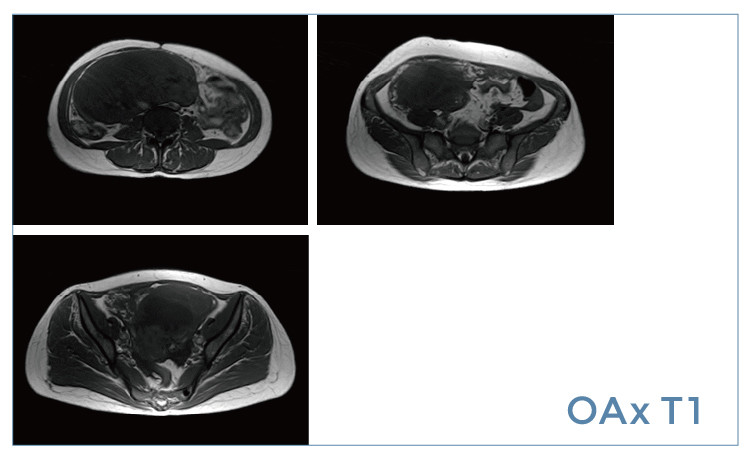

【朗润影像档案】磁共振影像病例分享(编号20190426)

【朗润影像档案】磁共振影像病例分享(编号20190419)

【朗润影像档案】磁共振影像病例分享(编号20190412)

【朗润影像档案】磁共振影像病例分享(编号20190405)